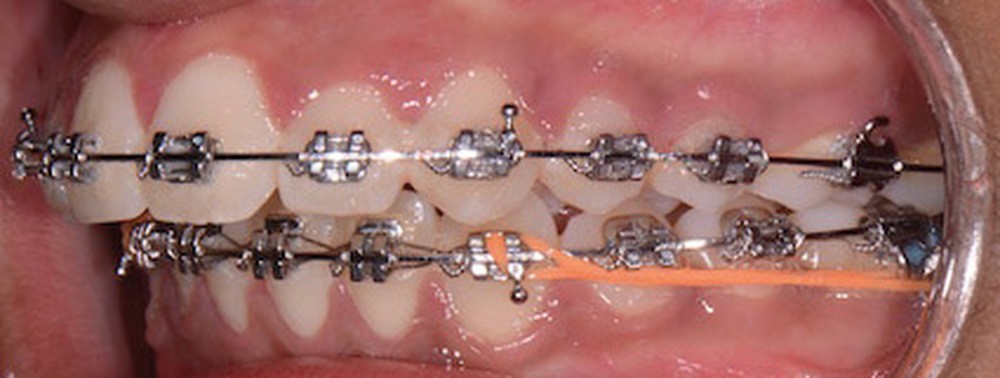

Nous équipons la patiente avec un appareil multi-attaches (.022 x .028 inch pré-informé Roth) mais nous n’avons pas activé l’arcade mandibulaire. La patiente est adressée au chirurgien maxillo-facial (Dr Gonzague Deffrennes, hôpital Beaujon) qui réalise l’avulsion des troisièmes molaires et la pose de plaques vissées avec émergence entre les premières et deuxièmes molaires mandibulaires dans l’axe des brackets (fig. 9). Étant donné l’absence d’encombrement au niveau incisif mandibulaire, nous pouvons rapidement mettre en place les tractions postérieures. Nous solidarisons ainsi le bloc antérieur de canine à canine et réalisons un recul en masse de l’arcade directement des canines aux plaques postérieures. La majeure partie du recul est faite sur un arc acier .018x.025 inch permettant le glissement. La force appliquée est de 250-300 g par côté.

Nous avons pu repositionner l’incisive mandibulaire de 8° (fig. 10), obtenir un surplomb correspondant à la classe II d’Angle et ainsi réaliser l’avancée mandibulaire. Le chirurgien accompagne celle-ci d’une génioplastie afin d’harmoniser le profil. Nous corrigeons la DDD par stripping des incisives mandibulaires ce qui permet de corriger encore de 1° l’axe incisif.